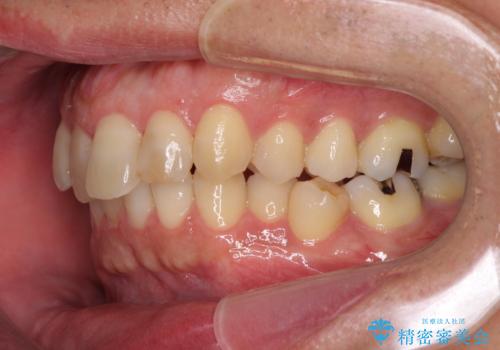

- 外に飛び出した側方の歯と、前歯のデコボコを気にして来院された患者様です。

IPR(歯と歯の間を削る)によってデコボコが解消するように設計し、インビザラインにより治療を行うこととしました。

治療途中で1年半以上通院されない時期があったため、後戻りが生じたことで治療期間が長くなってしまいました。

親知らずを抜去したことで、下顎のデコボコがきれいに解消されました。